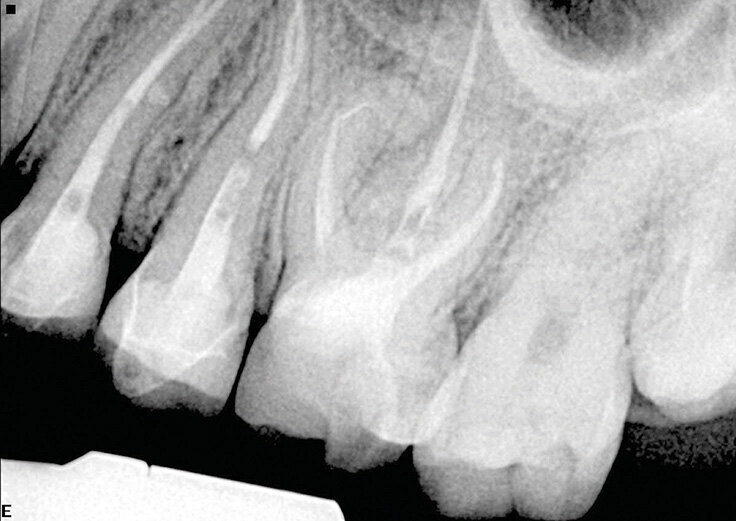

Slučaj 1 – Slika br. 2: Inicijalni periapikalni Rtg snimak

Slučaj 1 – Slika br. 3: Periapikalni kontrolni Rtg snimak nakon godinu dana od tretmana

Pacijent je upućen zbog nelagodnosti u donjim zubima koja je prerasla u pulsirajući bol. Nakon pregleda i rendgenskog snimanja, kod pacijenta je konstatovano da ima problema na prvom donjem molaru i premolaru. Prethodni kanal korena nije bio urađen na nivou standarda i izgleda kao obturacija sa jednim konusom (Slika br. 1). Pacijentu je predočen plan lečenja koji uključuje ponovno lečenje i premolara i molara i na kraju zamena obe krunice. Prošao sam kroz krunice za oba zuba u istoj sesiji. Kao što je ranije opisano, turpije koje sam koristio bile su Traverse 25 08 17 mm, a zatim se Zenflex 35-30-25 06 sužavaju do radne dužine. U ovom slučaju dodao sam konus 35 04 kao turpiju za proširenje na vrhu. Urađena je 3D obturacija pomoću elements IC za oba zuba. 12 meseci nakon tretmana pozvao sam pacijenta na kontrolu (Slika br. 2). Primetio sam da je zarastanje na oba zuba gotovo u potpunosti završeno, sa prelepom obturacijom sistema korenskih kanala i više izlaza. Krunica na molaru je zamenjena, ali na žalost krunica na premolaru nije, na snimku se vidi neka vrsta unutrašnjeg nakupljanja, te sam obavestio pacijenta da to može da ugrozi uspeh lečenja premolara.